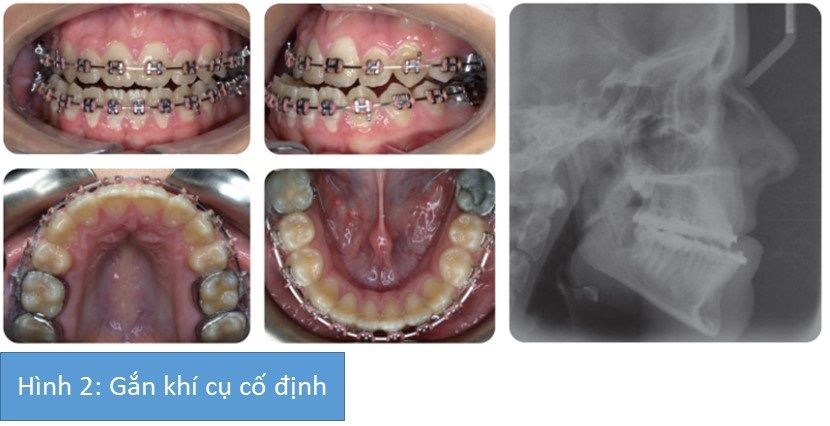

Sinh viên nữ 18 tuổi không hài lòng với khớp cắn và vẻ ngoài của các răng. Cô ấy có sức khỏe tốt và vui vẻ khi điều trị chỉnh nha bằng khí cụ cố định.

- tương quan xương hạng III với thiểu sản xương hàm trên và quá sản xương hàm dưới.

- Tỉ lê theo chiều đứng tăng

- Bất đối xứng xương hàm dưới với đỉnh cằm nằm bên phải

- Độ lộ răng cửa hàm trên giảm nhẹ

- Cắn hở phía trước (khoảng 1 mm)

- Cắn chéo răng sau 2 bên

- Lệch đường giữa hàm dưới